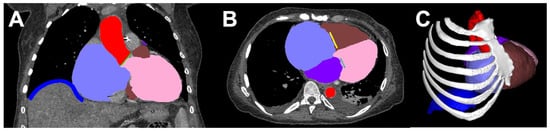

- Bertolini, M.; Rossoni, M.; Colombo, G. Operative Workflow from CT to 3D Printing of the Heart: Opportunities and Challenges. Bioengineering 2021, 8, 130. [Google Scholar] [CrossRef]

- Abudayyeh, I.; Gordon, B.; Ansari, M.M.; Jutzy, K.; Stoletniy, L.; Hilliard, A. A practical guide to cardiovascular 3D printing in clinical practice: Overview and examples. J. Interv. Cardiol. 2017, 31, 375–383. [Google Scholar] [CrossRef]